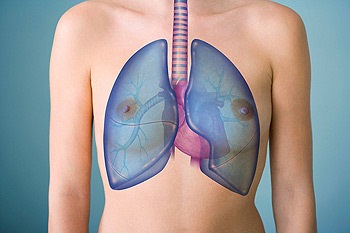

Pneumonie: modul în care plămânii de lucru

- Când inspirăm, aerul intră în trahee.

- Traheea se împarte în două bronhii, și ei, la rândul lor, la miile de mici.

- La sfârșitul fiecărui pulmonar este un balon. Aici din sange furnizat preia oxigenul și dioxidul de carbon dă. Când se produce inflamație, bule nu funcționează corect, procesul de schimb de gaze este afectata, iar organismul nu dispune de oxigen.